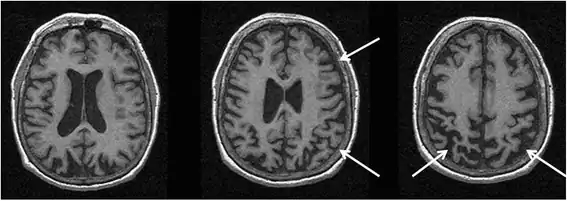

O objectivo da realização de uma tomografia computorizada ou de uma ressonância magnética ao cérebro é excluir uma lesão estrutural, como um tumor, abcesso, hematoma ou enfarte. Na ausência destas lesões, alguns achados podem apoiar o diagnóstico de degeneração corticobasal, como a atrofia cortical assimétrica, especialmente frontoparietal, com a atrofia mais proeminente contralateral ao lado mais severamente afectado clinicamente (Fig. 2).[65][66][67][68][69][70] O ventrículo lateral no hemisfério cerebral mais afectado pode também ser ligeiramente maior do que o oposto. Uma atrofia assimétrica nos pedúnculos cerebrais pode estar presente (Fig. 3).[71] Outros achados de RM relatados na síndrome corticobasal incluem atrofia do segmento médio ou posterior do corpo caloso (Fig. 4),[72] alterações de sinal hiperintensas laterais ao putâmen,[65] atrofia do putâmen,[73] e alterações subcorticais subtis do sinal hiperintenso no córtex motor ± somatossensorial. [74]

Estes são frequentemente achados subtis e a sua presença ou ausência não deve alterar o diagnóstico clínico da síndrome corticobasal. É importante salientar que a maioria dos casos em que estes achados de Ressonancia magnética foram identificados não tiveram degeneração corticobasal verificada post-mortem. Na única série de pacientes com a síndrome corticobasal associada à patologia degeneração corticobasal, síndrome corticobasal associada à patologia não-degeneração corticobasal e patologia de degeneração corticobasal associada a características clínicas não-degeneração corticobasal, nenhum desses achados de Ressonancia Magnética foi considerado adequadamente sensível ou específico para a síndrome corticobasal.